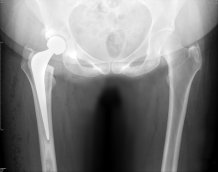

A hip replacement principally consists of two components, a stem with ball and another that replaces the socket. There is variation in how these parts are fixed to the bone, as well as in the materials used to create the bearing (contact) surface. In 2017, there were over 822 different combinations of hip replacements (stem with ball and cup) implanted in England and Wales, but the Royal Devon & Exeter NHS Foundation Trust (RD&E) has used one type of stem in combination with three designs of  cup in the last 14 years. In the RD&E,  only 1.7 per cent of hips needed to be re-done 14 years after the hip replacements were put in, but in the rest of the country this figure was 2.9 per cent. Given that about 100,000 people have a hip replacement every year, this difference could lead to many more patients needing further surgery.

Professor John Timperley, of the University of Exeter and the Royal Devon & Exeter NHS Foundation Trust (RD&E), said the research demonstrated the high quality of the Exeter Hip implants, designed by Professor Robin Ling and Dr Clive Lee in a partnership between the University and the hospital trust. The Exeter Hip, which is approaching its 50th anniversary, is now widely used globally, including at the RD&E – the hospital with the best outcomes in the study.